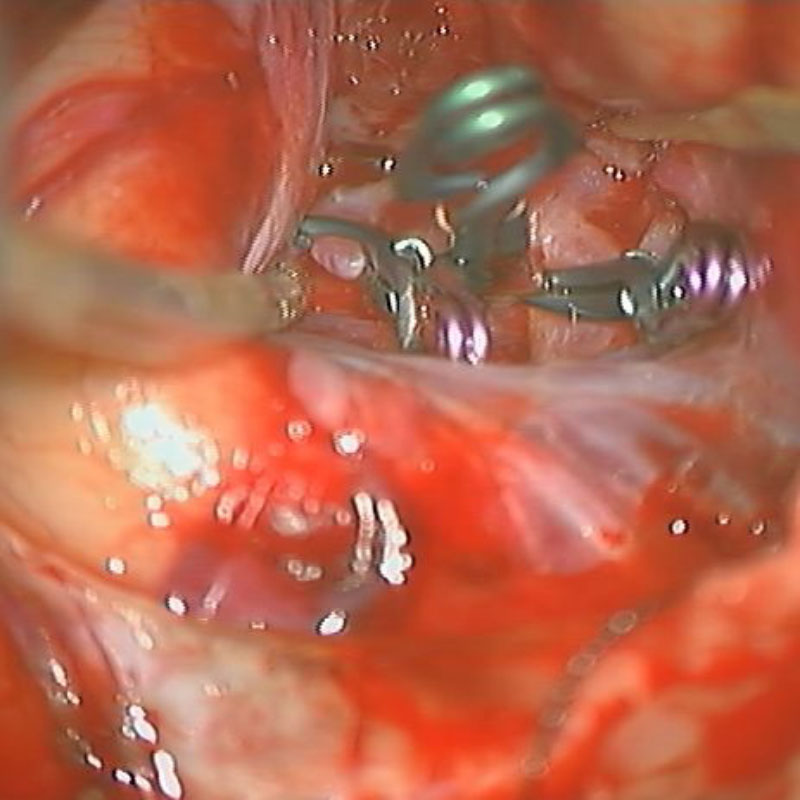

クリップ後

術後血管撮影